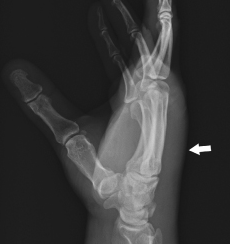

David Effron, MD; Jimmy Y. Saade, MD, FACEP; Ergent M. Zhiva, MD; Anthony M. Salibi, MSc

<p>A 50-year-old man, who is right hand dominant, presents to the emergency department (ED) with swelling of the left hand and intense pain. He is an intravenous drug user with multiple prior...